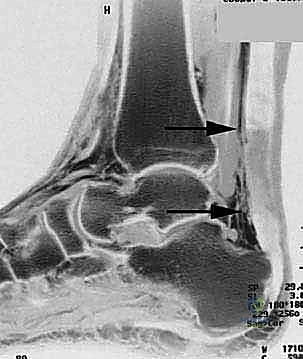

Imaging: While clinical diagnosis is often sufficient, for chronic ruptures, MRI or ultrasound is invaluable. We use these to:

* Quantify the true gap size: This dictates our surgical strategy.

* Locate the retracted tendon ends: Essential for planning our incision and dissection.

* Assess muscle atrophy and fibrosis: This helps prognosticate functional recovery.

FIG 1 • A large palpable gap can usually be felt between the ruptured ends.